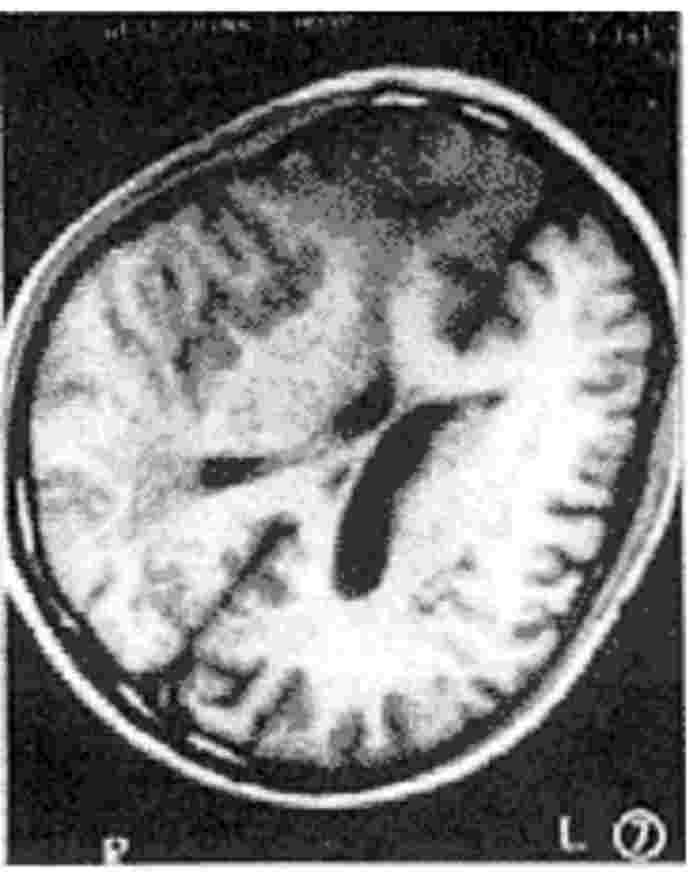

图4.57 髓质即为白质

图4.58 双侧大脑白质见多